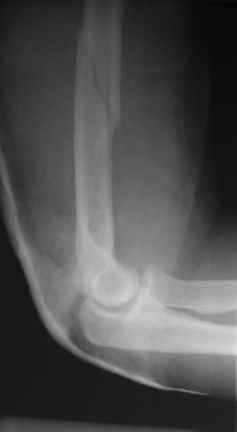

Огромное спасибо всем принимающим участие в дискуссии. Вначале отвечу на поступавшие персональные вопросы: 1. обстоятельства травмы - соревнования по армрестлингу (от себя замечу, что у военных нередкая травма в последнее время! На мой взгляд это связано с вовлечением в это дело неподготовленных людей - командирам нравится, т.к. в плане реквизита намного легче организовать чем традиционное перетягивание каната...). 2. в отношении провокационной составляющей - она присутствует, но лишь в той степени в какой любое инициирование дискуссии несет в себе элемент провокации... 3. про актуальность консервативного лечения - мне кажется это актуально всегда и при любой локализации если врач владеет методом, например, часто наблюдал великолепные функциональные результаты консервативного лечения переломо-вывихов голеностопных суставов... Тут только надо помнить, что "консервативное" это тоже лечение (контроль, тяги, перекладывание повязок), а не просто накладываем гипс и через энное время говорим, что не получилось и берем на операцию.

Теперь непосредственно по больному. Лечим функциональной повязкой, добились вот чего (приложение). Будем признательны за дальнейший комментарий - мое мнение, что можно продолжить без операции.